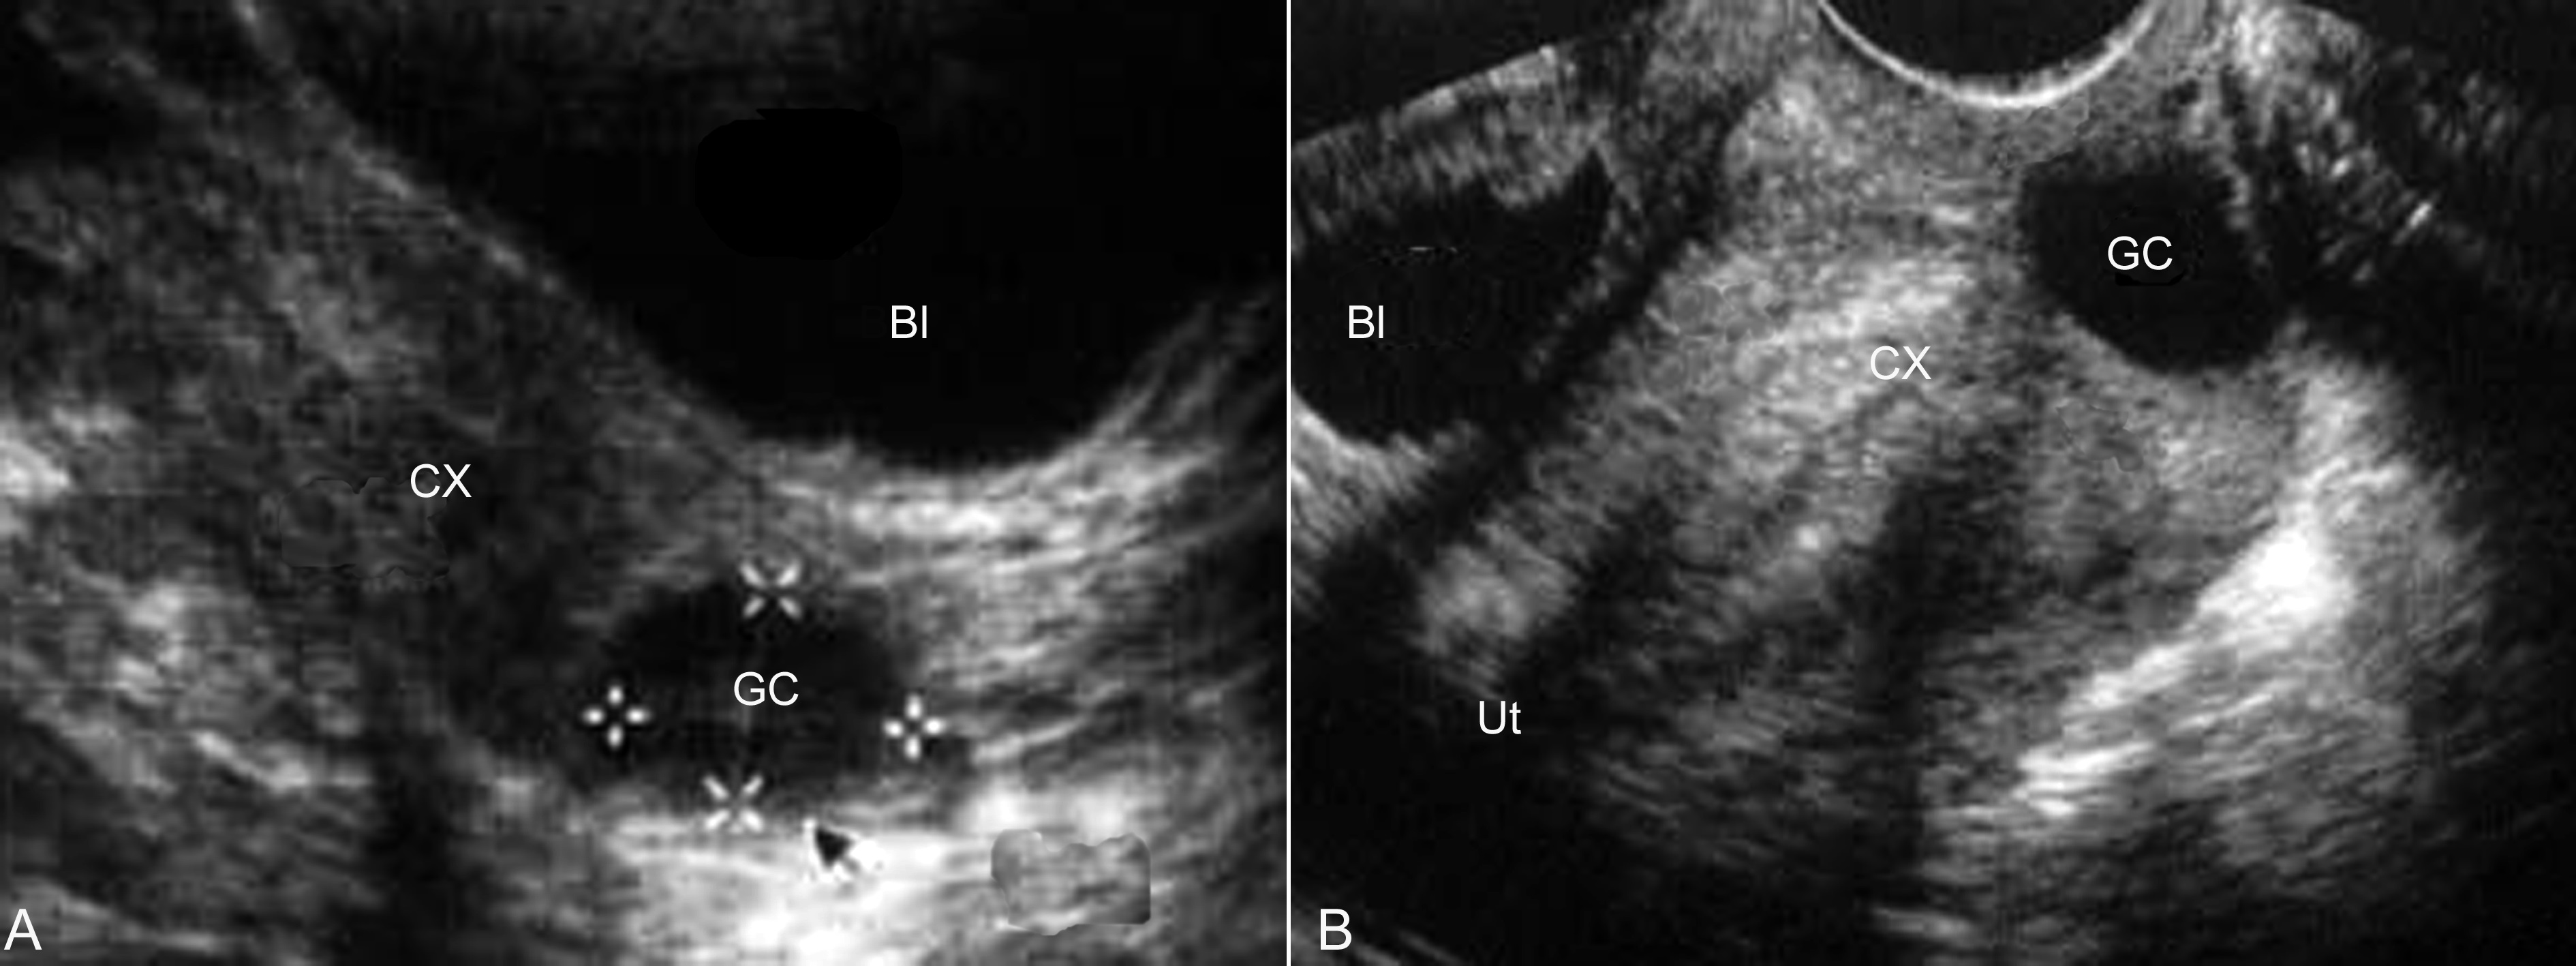

超声显象检查Wolffian氏管囊肿显示为妊娠子宫的一侧的无回声,位置常较卵巢病变低,形态规则,边缘清晰,内部透声良好,有时可以在其内部显示纤细的分隔回声;如果显示内部有实质性乳头状回声是要警惕有恶变的可能;也有位于腹膜后的报告;单纯依靠声像图难以与卵巢的上皮性囊肿进行鉴别,但卵巢的显示及囊肿下极达到子宫颈水平是应首先考虑为胚胎遗迹囊肿;阴道旁的胚胎遗迹囊肿可以发生在阴道的任何部位,以阴道前外侧多见;超声检查多显示为梭形或椭圆形无回声区,形态规则,边缘清晰(图2)。由于囊肿的压迫,可以显示阴道向一侧突出,位置较低时可以向外阴突出。

图2阴道旁囊肿声像图

A:TAU,膀胱(Bl)后方、宫颈(CX)显示阴道旁囊肿(GC)无回声

B:TVU,显示同上